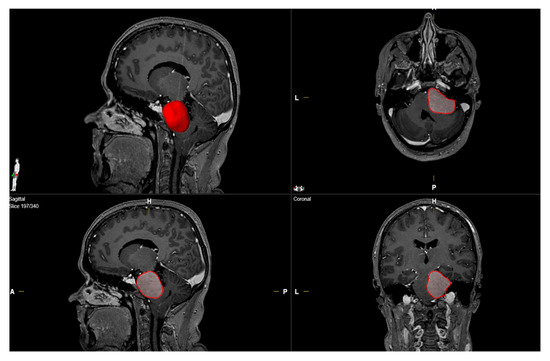

1. Introduction

2. Materials and Methods